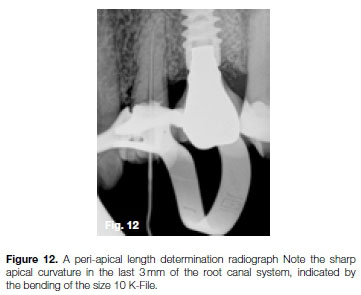

The patient, a 54 year old female, presented with irreversible pulpitis on her maxillary left first premolar, caused by extensive decay under a previously placed porcelain veneered crown (Figure 11). After removal of the defective crown and decay a core build-up was done prior to root canal treatment. A size 10 K-File was negotiated to full working length and confirmed radiographically (Figure 12). Note the sharp apical curvature in the last 3mm of the root canal system.